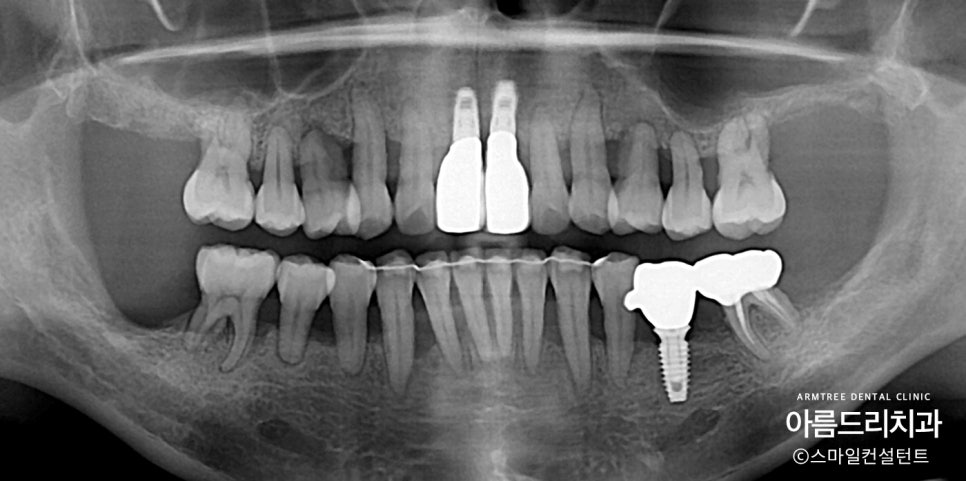

교정 기간이 길지 않았지만

그래도 뼈가 워낙 없기 때문에

임플란트 치료 시기를 지속적으로

체크하고 교정진료가 끝나기 전에

적절한 조치를 취해야 합니다.

교정이 끝날 때까지 보철의사가

상황을 체크하지 않으면

교정이 끝난 후에 임플란트 치료를 위해서

추가적인 치료기간을 몇개월 더 갖게됩니다.

결국 치료기간이 길어진다는 얘기죠.

그렇지만 보철의사가 지속적으로 체크하면

보철치료와 교정치료가 동시에 끝나도록

치료타이밍을 맞출 수 있습니다.

제가 보철을 위한 교정진료를 하는 이유입니다.

원칙적으로 위 아래 28개의 치아가 정상이지만

24개의 치아만 만들었습니다.

발치교정하는 분들의 경우

치아가 들어갈 공간이 없어서

4개의 치아를 발치하고 24개의 치아로

지내는 사람이 많습니다.

24개의 치아로도 먹고 지내는 데에는

아무 문제가 없기 때문에

이번 케이스에서도 굳이 임플란트를

많이 심지 않았습니다.